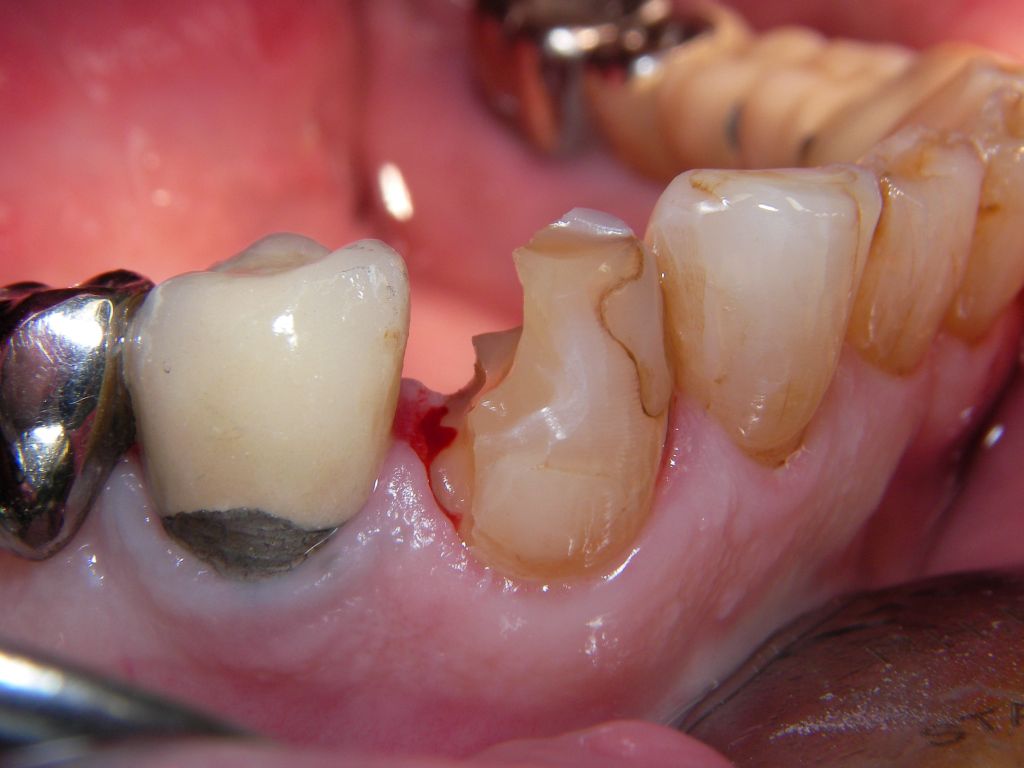

![]() | Von den 3 Kompositfüllungen des Zahnes sollen die beiden zu den Nachbarzähnen hin, rechts und links ("mesial" und "distal"), ersetzt werden. Ich habe das nacheinander gemacht, weil die Füllungen jeweils sehr groß waren und sonst die Situation schwieriger zu kontrollieren gewesen wäre. |